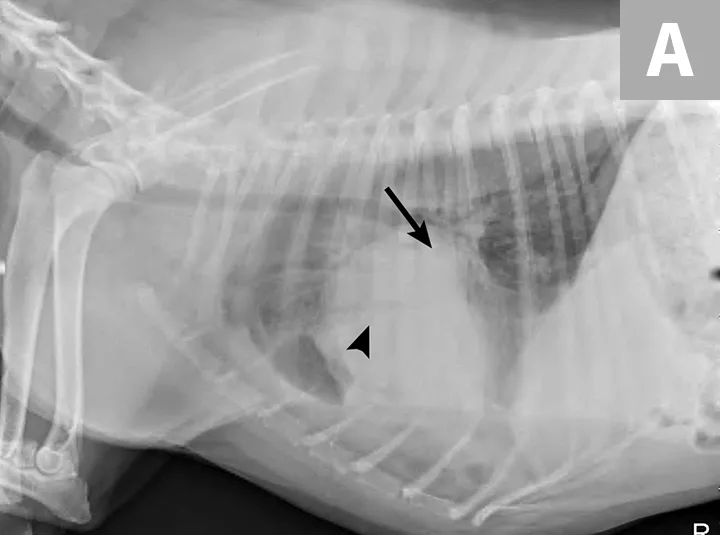

Right lateral thoracic radiographs revealed a large amount of fluid/soft tissue opacity obscuring the cardiac silhouette. Ventrodorsal radiographs showed increased soft tissue opacity in the left hemithorax, primarily in the cranial and middle lung fields. A mild interstitial pattern, a pleural fissure line, and border effacement of the heart were noted in the left hemithorax (Figure 1).

FIGURE 1A

Right lateral (A) and ventrodorsal (B) thoracic radiographs obtained prior to thoracocentesis demonstrating a mild interstitial pattern, moderate pleural effusion, soft tissue opacity in the left cranial and middle lung field, border effacement of the heart, and a pleural fissure line (arrows)

Radiography findings suggested a combination of pulmonary and pleural space disease. Differential diagnoses included pleural effusion (eg, hemothorax, pyothorax, chylothorax, hydrothorax, neoplasia) and pleural space mass or mass effect (eg, neoplasia, lung lobe consolidation or torsion, abscess/granuloma).